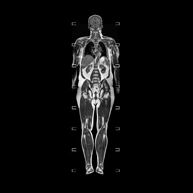

- Full body MRI

This non-invasive diagnostic procedure uses an electromagnetic field and radio waves (from a transmitter and receiver) to acquire high-definition anatomical images of the whole body. It is a radiation-free procedure. It is a very important test in the search for metastasis in patients with known neoplasia. No prior preparation is required. No paramagnetic contrast (gadolinium) is used.